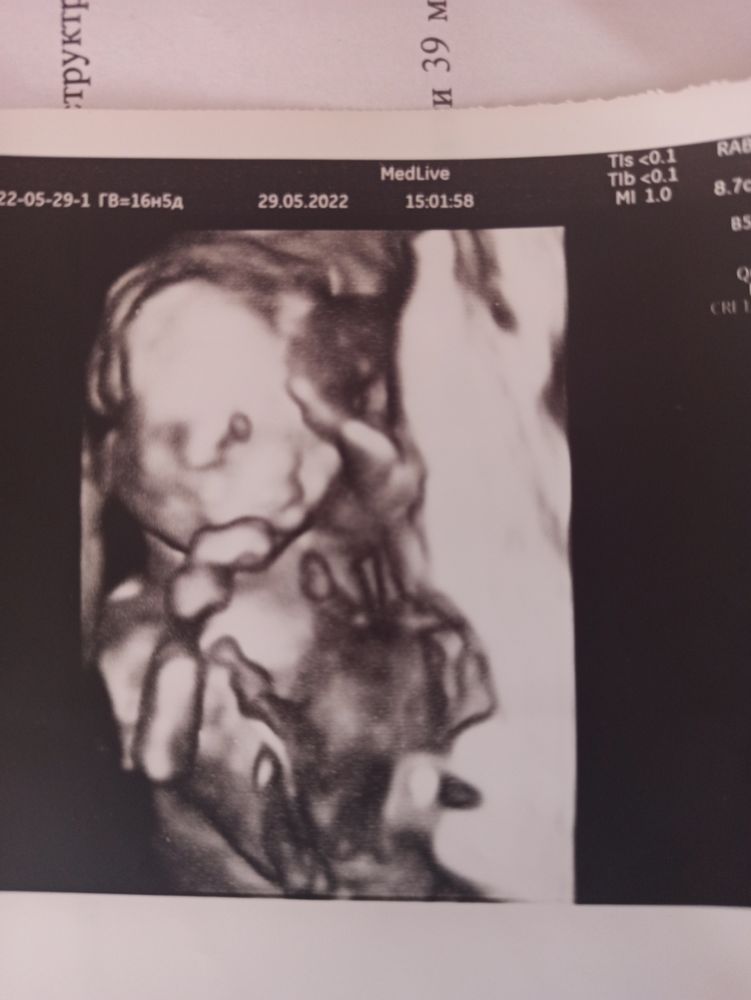

Привет девчонки, как думаете мальчик или девочка? по узи сказали что девочка, но по ощущениям как будто мальчик, фото узи 16-17 недель

А нет фото не в 3д? Просто у сыночка в 16 недель намного больше торчали пипирка. А вот такая маленькая может оказаться клитором